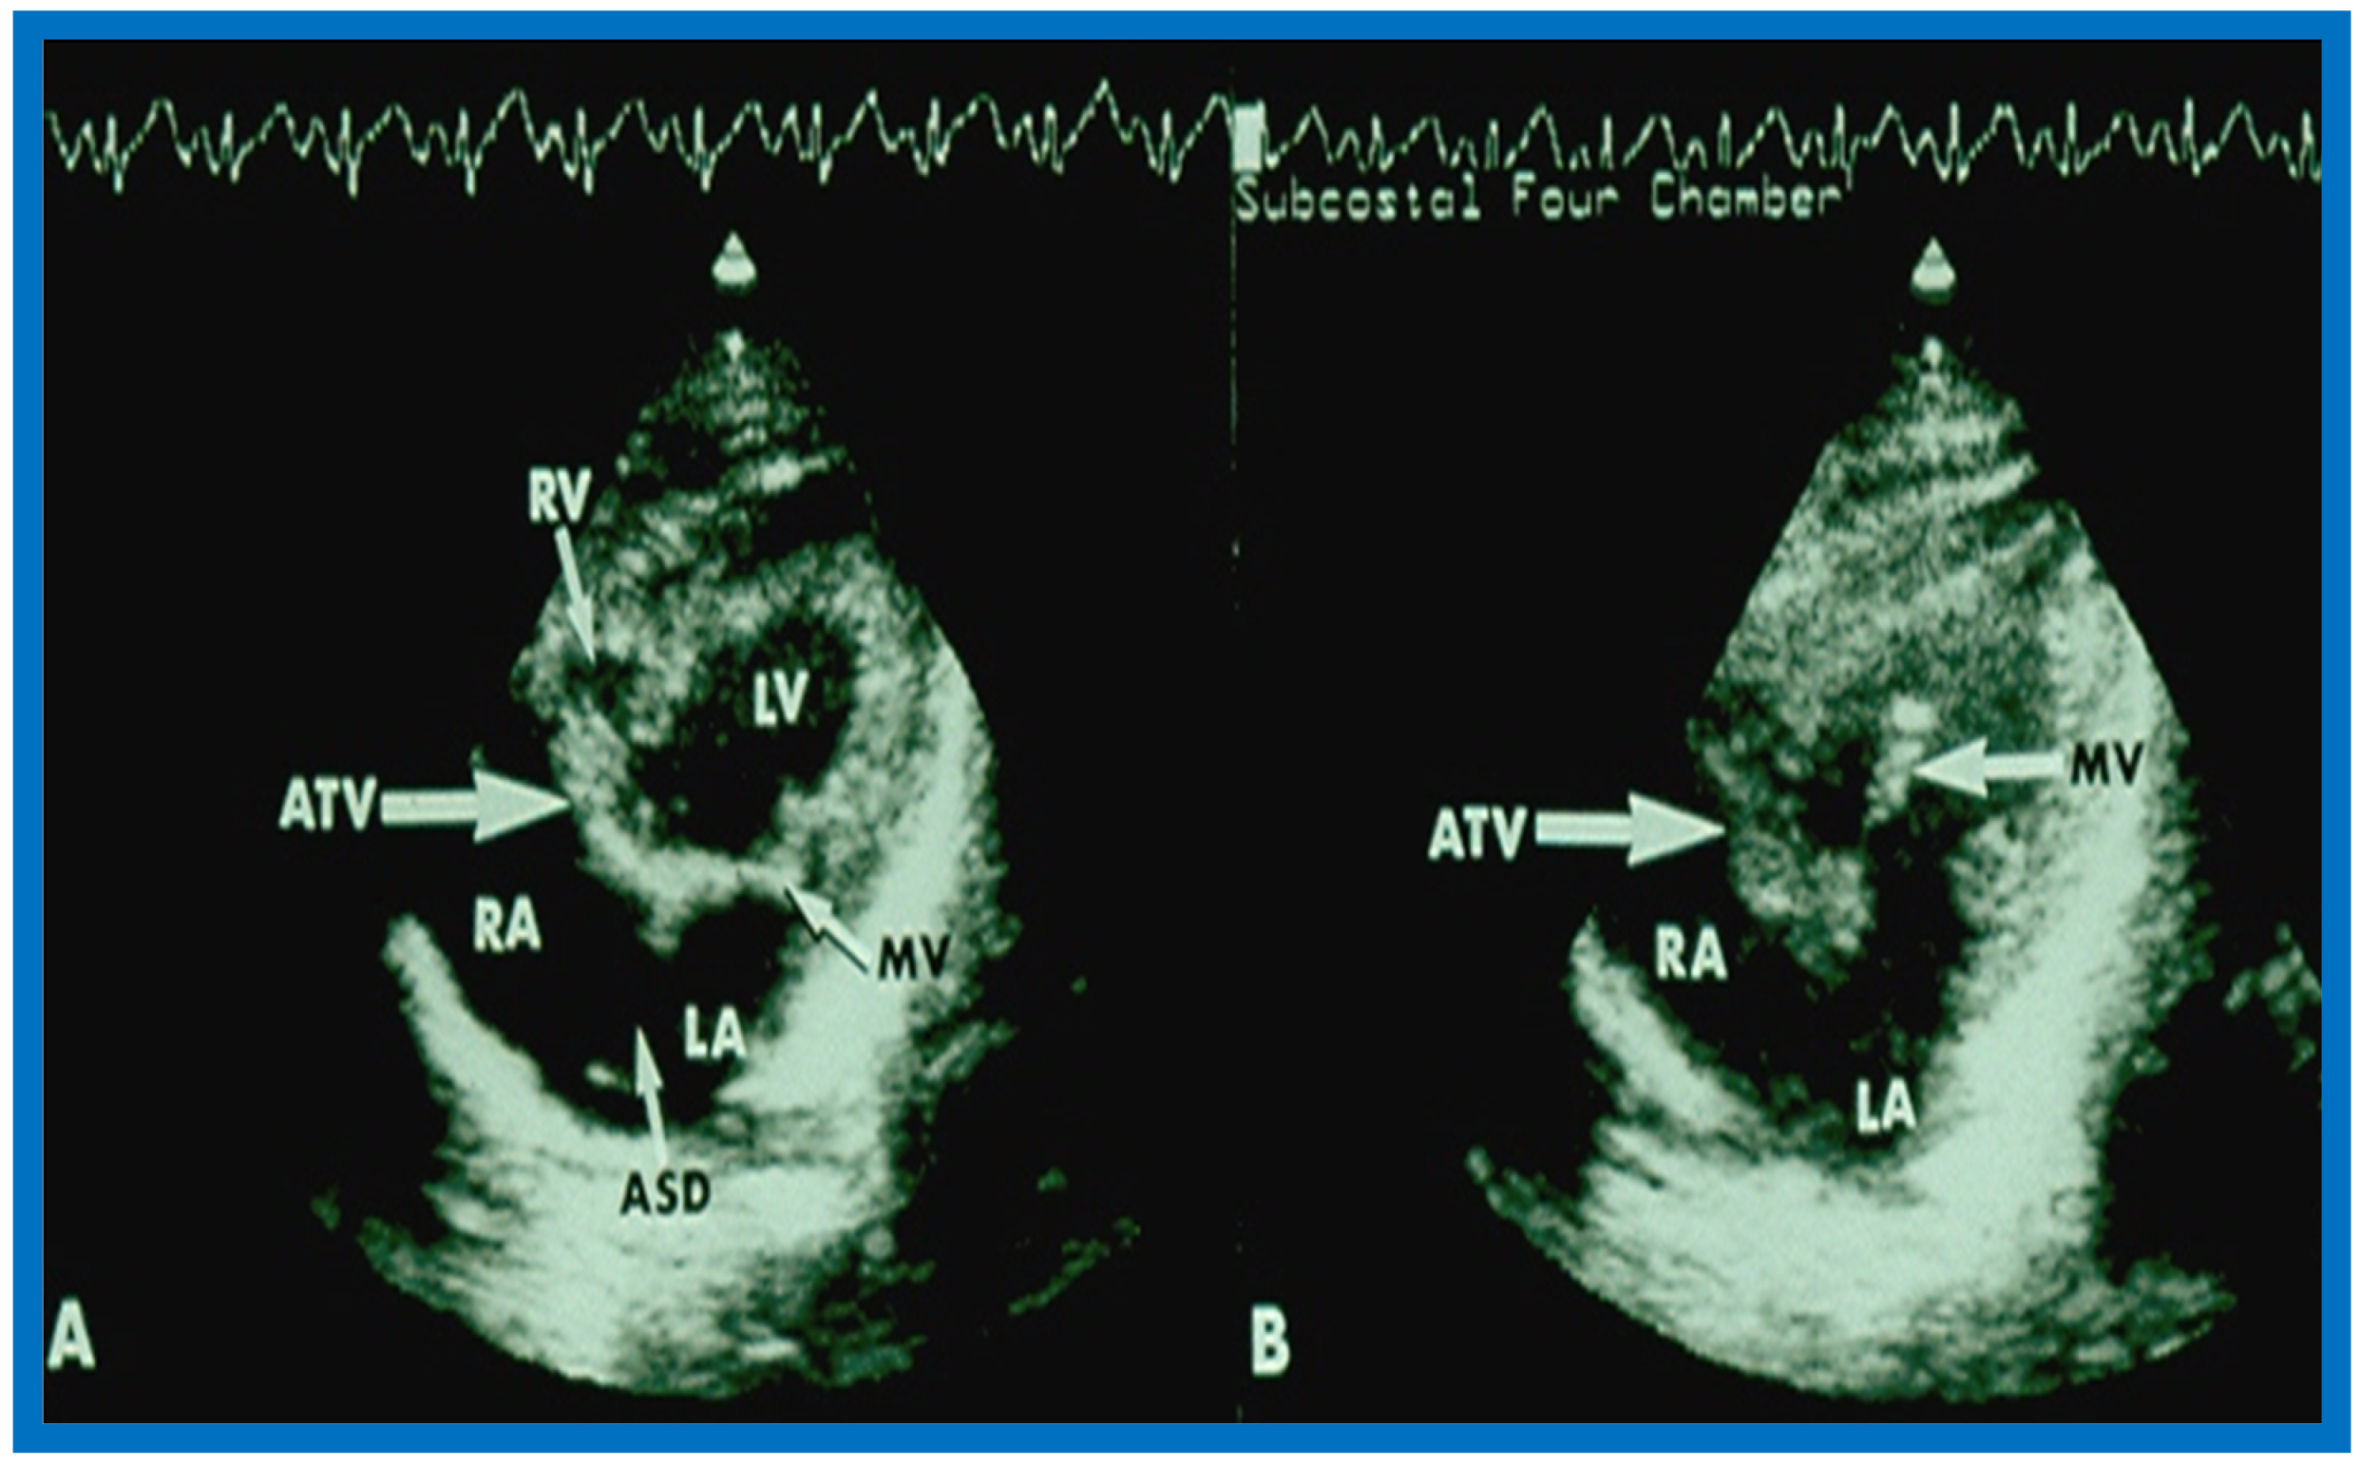

More recently, the author reviewed the echo-Doppler evaluation of tricuspid atresia [37,38,39]; these findings will be presented. M-mode echocardiography, while not diagnostic, is useful for evaluating the size of the left atrium (LA) and left ventricle (LV) and LV function. On 2D echocardiography, the atretic tricuspid valve is visualized directly as a dense band of echoes at the site where the tricuspid valve should be in the most frequent muscular type, as shown in Figure 14, Figure 15, Figure 16 and Figure 17. This anatomy is better demonstrated in apical and subcostal four-chamber views than in other views. The other types, namely membranous, valvular, Ebstein’s, atrioventricular septal and unguarded valve with muscular shelf (Figure 18) [40], are rare and may also be recognized on 2D echocardiography.

Following the demonstration of the atretic tricuspid valve, the sizes of the cardiac chambers were evaluated both by M-mode (Z scores) and 2D echocardiography; enlarged RA, LA and LV, and a small RV, were seen (Figure 14, Figure 15, Figure 16 and Figure 17). Pulsed (not shown) and color Doppler (Figure 19) studies were helpful in illustrating the right-to-left shunt across the patent foramen ovale or atrial septal defect. Contrast study using agitated saline with 2D imaging clearly demonstrated successive opacification of the RA, LA, LV and then the RV in that order, but such a study is not necessary for diagnosis.

Figure 15.

Selected video frames from subcostal four-chamber view of a two-dimensional (2-D) echocardiographic study demonstrating atretic tricuspid valve (ATV) (thick arrow), represented by a dense band of echoes between the right atrium (RA) and hypoplastic right ventricle (RV). In (A), the mitral valve (MV) is closed, while in (B), it is open. Note the improvement from the pictures shown in Figure 14. LA, left atrium; LV, left ventricle. Reproduced from Rao P.S. [35].